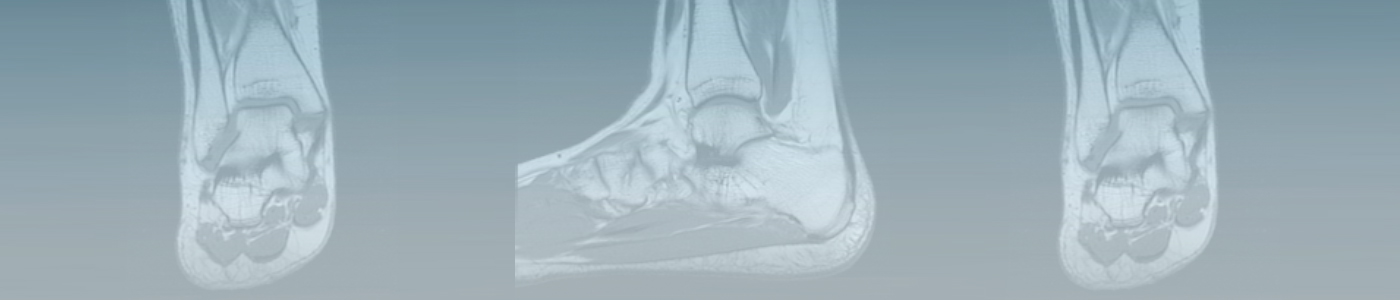

MSK MR Virtual Course — Ankle/Foot Case Review

The MSK MR Ankle/Foot Virtual Course is designed to provide the practicing radiologist with experience in the technique and the interpretation of MR imaging of the ankle/foot. Led by William Morrison, MD, FACR, from Thomas Jefferson University, you will have the opportunity to:

• Identify the normal appearances of important anatomic structures on MR imaging of the ankle/foot.

• Detect common abnormalities of frequently injured tendons, ligaments and osteochondral structures on MR imaging of the ankle/foot.